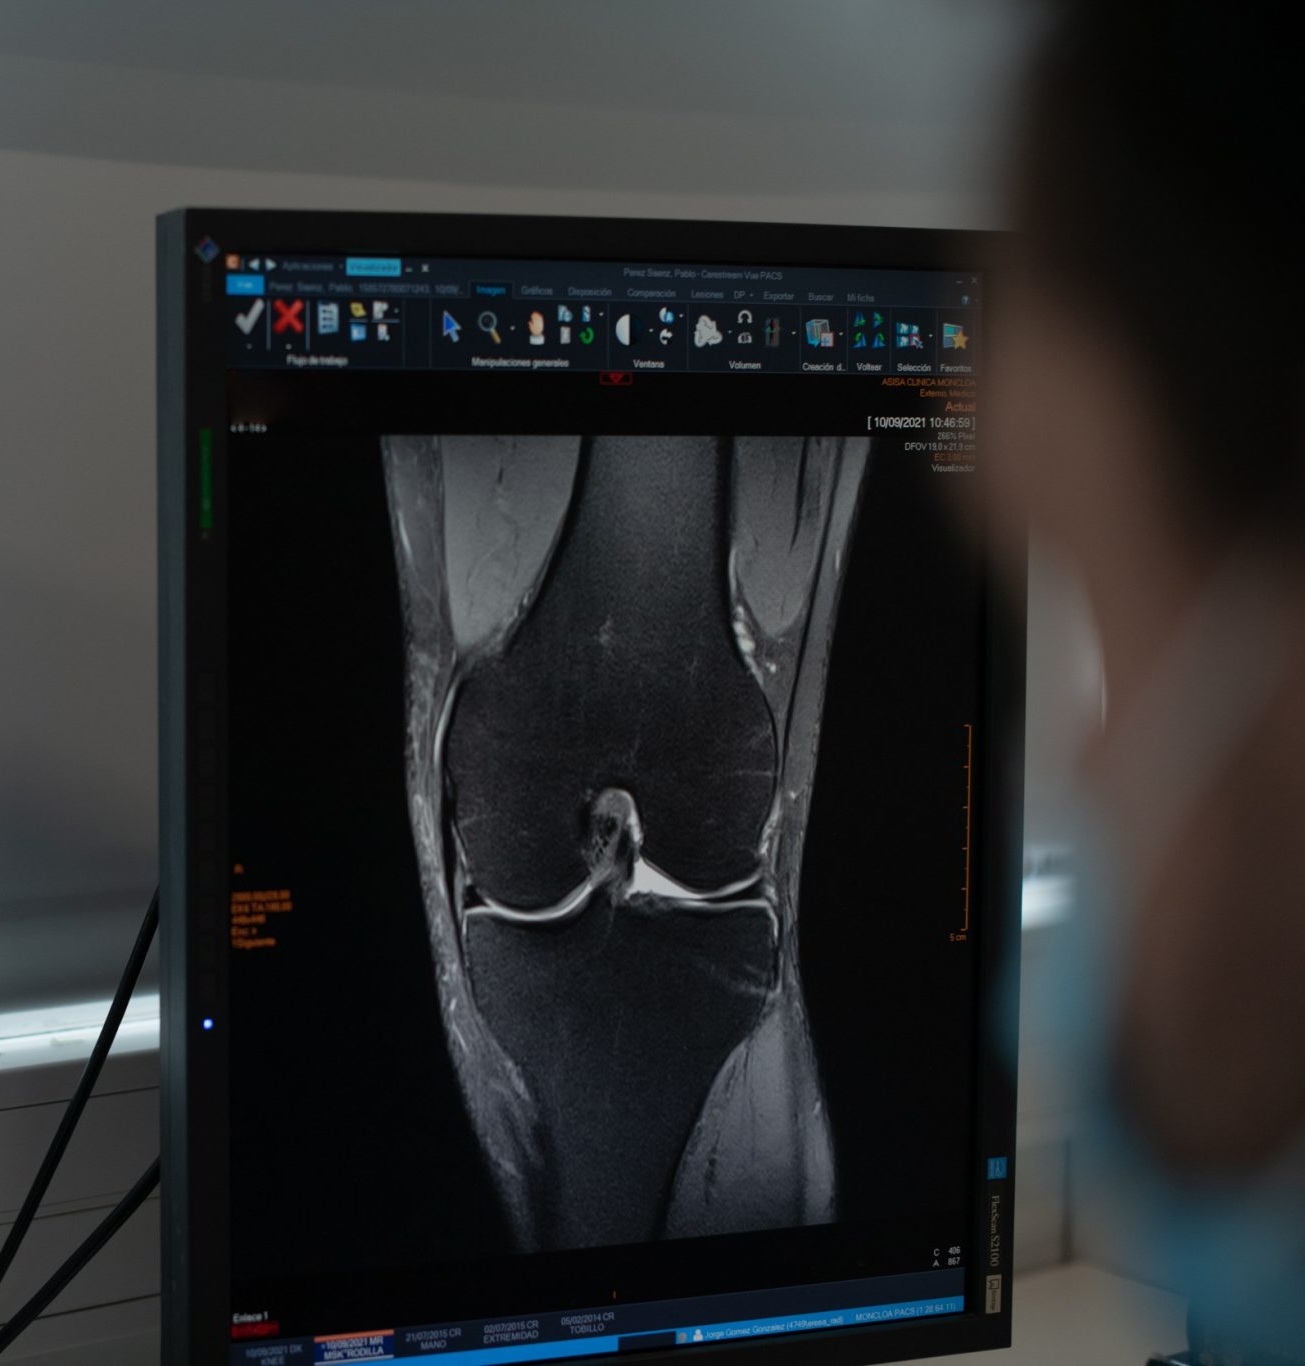

Ofrecemos un servicio completo de Radiología General y Avanzada, que abarca desde radiología digital y ecografía hasta radiología contrastada y TAC dental 3D (CBCT).

Utilizamos equipos de última generación, que garantizan mínima radiación, máxima precisión para determinar diagnósticos rápidos, seguros y de alta calidad.

Centro de Diagnóstico Granada utiliza radiología computerizada digital, una técnica que reduce significativamente la dosis de radiación recibida por el paciente y mejora la nitidez y calidad de las imágenes, lo que permite diagnósticos más precisos. Fue uno de los primeros centros de España en implantar esta tecnología, en 1996, sustituyendo las placas radiográficas tradicionales por detectores digitales que almacenan las imágenes en formato informático, con posibilidad de impresión o transmisión electrónica.

Esta innovación ha permitido eliminar los procesos de revelado químico, reduciendo el impacto ambiental y avanzando hacia una radiología más sostenible, mediante la impresión en papel, grabación en CD o envío digital al médico. Las imágenes se analizan en monitores de alta resolución, seleccionando solo las más relevantes para su impresión y almacenando el resto en formato digital.